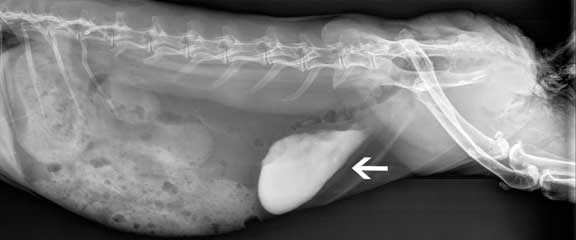

It never hurts to be thorough during this pre-anesthetic exam and take a radiograph (X-ray). The following 3 radiographs, on rabbits that were seemingly normal, show why.

This one has a problem with calcium sludge in the urinary bladder. Our Calciuria page has more details.